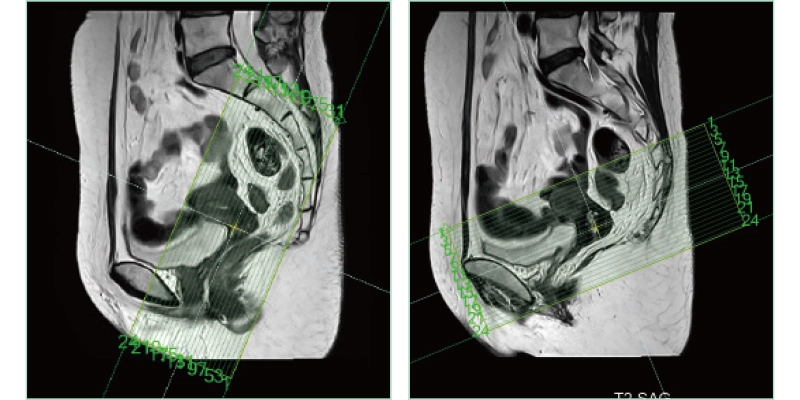

AutoPose FemalePelvis

AutoPose Knee

The slice line setting support function, "AutoPose," automatically sets the slice lines as soon as the scanogram is scanned.